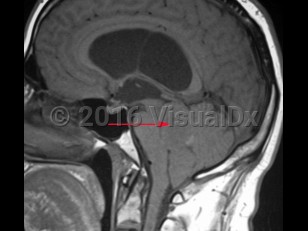

An ependymoma is a tumor of the brain or spinal cord arising from ependymal cells. Ependymomas account for 4% of central nervous system (CNS) tumors in adults and 10% of CNS tumors in children. In children, they are most often located in the 4th ventricle and posterior fossa, whereas in adults, they are more frequently located in the spinal cord. In the spinal cord, they tend to occur centrally, causing symmetric cord expansion. Peak incidence in adults occurs between 30 and 40 years of age.